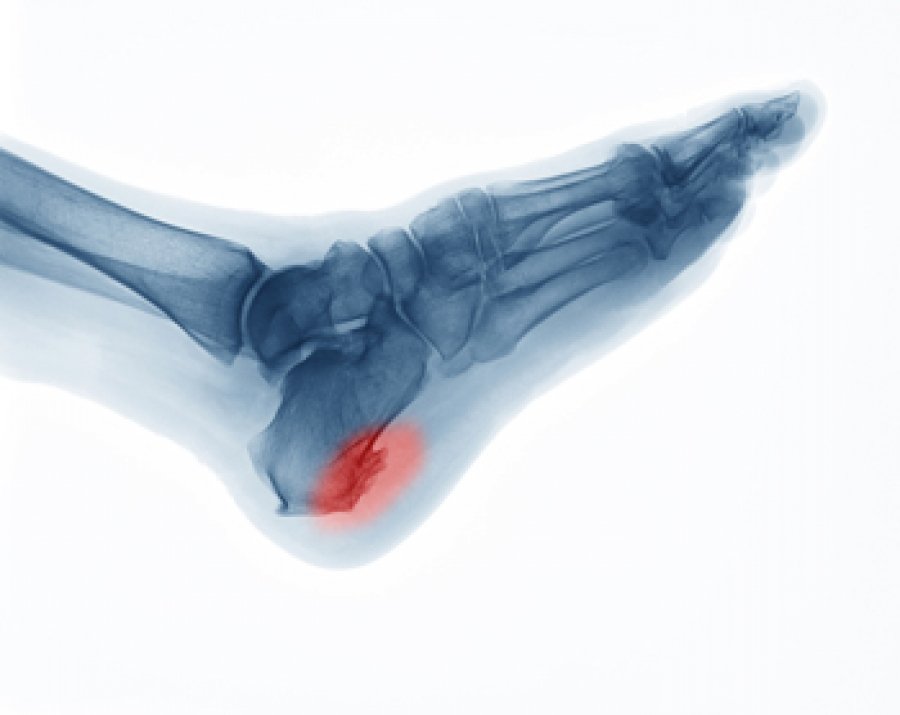

Bone spurs in other areas

While bone spurs are commonly associated with joint-related issues, they can also occur in other areas of the body. For example, bone spurs can develop on the spine, which can be caused by degenerative changes or conditions like spinal stenosis. Similarly, bone spurs can form on the heels, known as heel spurs, which are often associated with plantar fasciitis. The risk factors for these types of bone spurs may vary, but maintaining overall musculoskeletal health and addressing specific condition-related risk factors can help prevent or alleviate their formation.